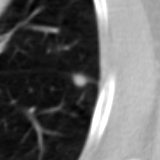

The current study focuses on lung nodule retrieval from a database of CT scans, where patches taken from CT slices of pulmonary nodules are to be mapped into an embedding. LIDC-IDRI [5] is a dataset of thoracic CT scans of 1,010 patients. All the scans were annotated by up to four radiologists, where each one identified, segmented and evaluated separately the lung nodules of a diameter above . Their evaluation also included ratings for a set of 9 characteristics: Subtlety, Internal structure, Calcification, Sphericity, Margin, Lobulation, Spiculation, Texture and Malignancy. The rating system was based on a discrete score of 1-5. Four examples of nodule patches are illustrated in Figure 2: 2 benign (a, b) and 2 malignant (c, d). A rounded vector of the mean rating is bellow each nodule, with the characteristics ordered according to the listing above. The most prominent difference between a and b is the calcification: 3 (solid) and 6 (absent) accordingly. d compared to c has a more defined margin, is more lobulated, but less spiculated. The malignancy score is used to define malignancy classes: score of 1-2 is benign, score of 3 is unknown, and a score of 4-5 is malignant.

(a) Benign

3, 1, 3, 3, 4, 3, 1, 5, 1

(b) Benign

3, 1, 6, 5, 5, 1, 1, 5, 2

(c) Malignant

5, 1, 6, 3, 3, 4, 1, 5, 5

(d) Malignant

4, 1, 6, 3, 4, 2, 2, 5, 4